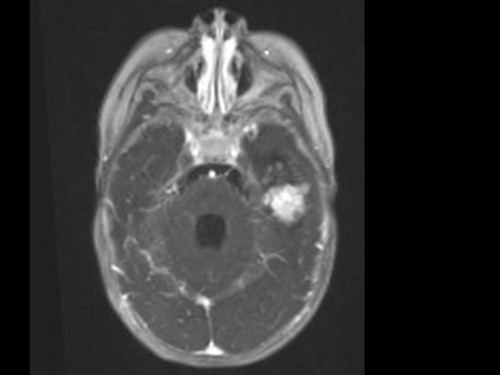

10 Monate altes Mädchen. Der Kinderarzt stellt fest, dass das kleine Mädchen einen recht großen Kopfumfang hat, nicht mit den Augen fixiert und anscheinend auch nicht richtig sehen kann. Damit bestätigt er die größten Befürchtungen der Eltern, denen in den letzten Wochen aufgefallen war, dass ihre Tochter nach keinem Spielzeug mehr greift und sie nur dann anlächelt, wenn sie zu ihr sprechen.

Bildgebung - MRT